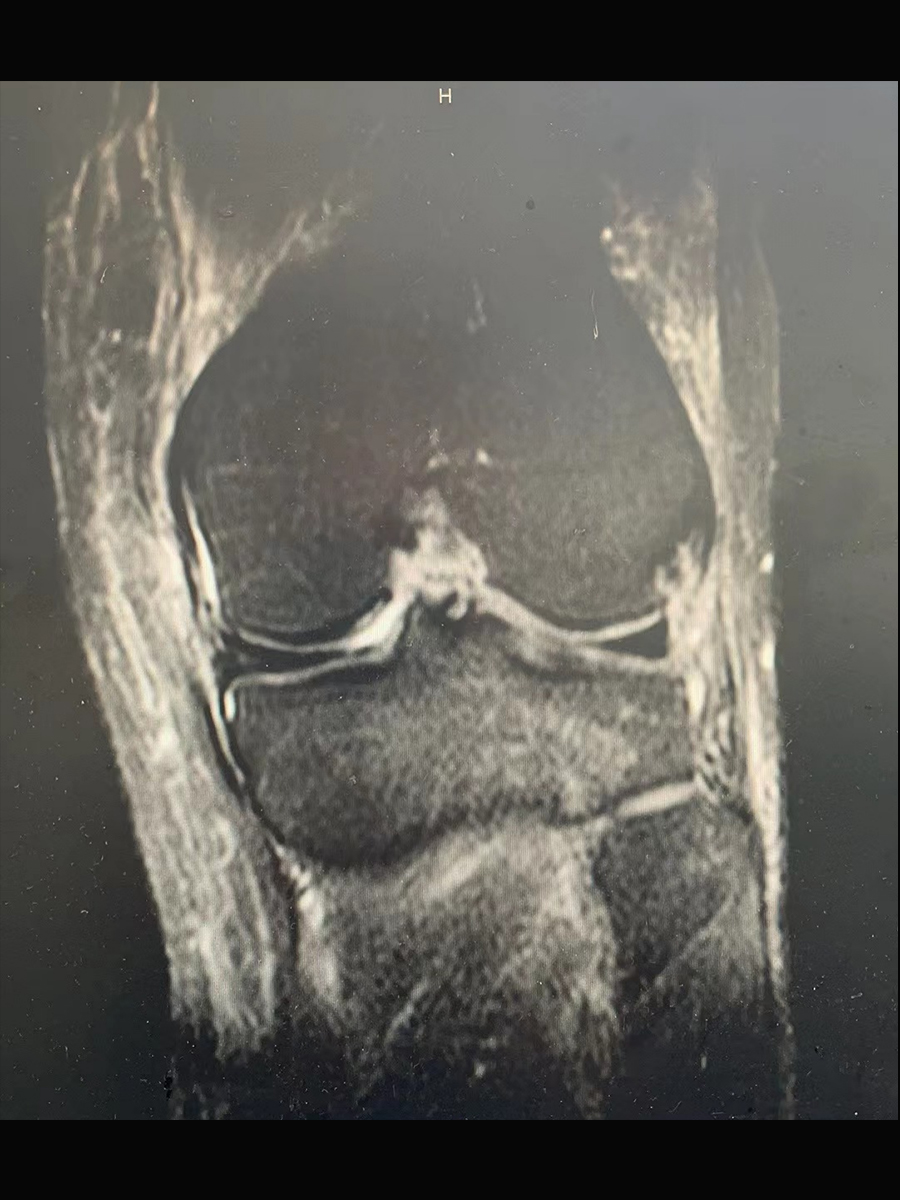

摘要:患者为33岁男性,在篮球运动过程中与他人发生撞击,导致膝关节扭伤,引起膝关节肿胀、疼痛等表现,就诊后通过核磁共振检查,确诊为前十字韧带断裂。建议住院治疗,经过关节镜下前十字韧带重建手术,以及康复锻炼,膝关节疼痛、肿胀缓解,灵活性和功能明显改善。

患者自述喜欢运动,每周定时参加小区内的篮球比赛,在比赛中和别人撞了一下,感觉膝盖扭了,随后膝关节出现肿胀、疼痛、活动受限,在关节肿胀减轻后出现关节不稳症状。考虑是打篮球时膝关节扭转过度牵拉前十字韧带,导致前十字韧带断裂,通过核磁共振检查确认前十字韧带连续性中断,由此确诊为前十字韧带断裂。就病情与患者及家属进行详细沟通后,同意住院治疗。